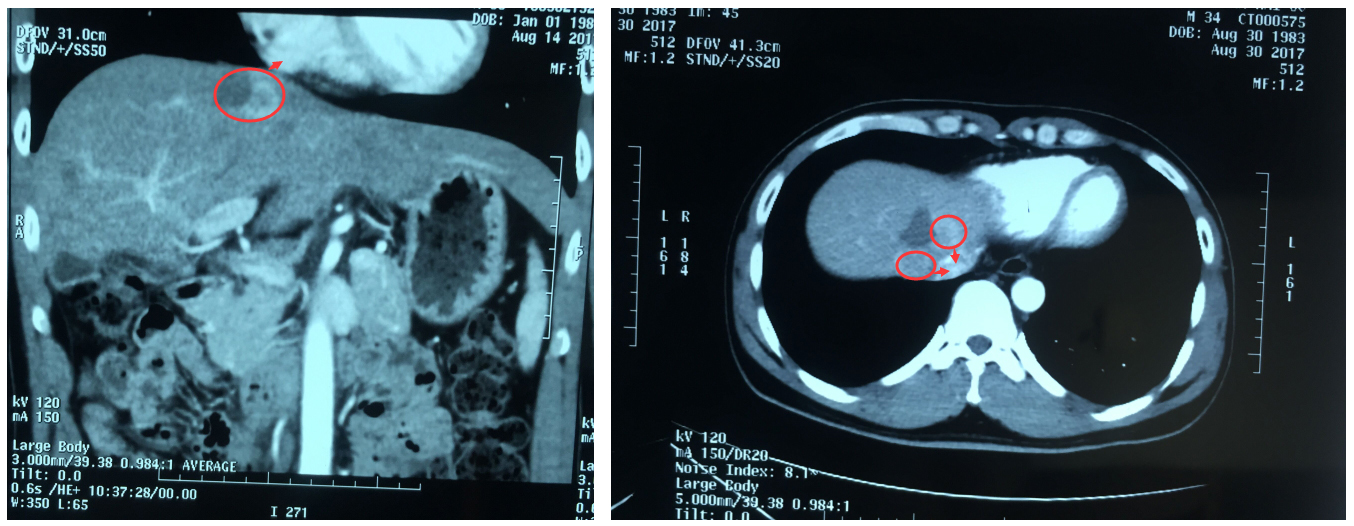

2017年9月1日上午,阮先生在气管插管全身麻醉状态下进行了纳米刀消融术,由白海山主任主刀,在CT扫描定位下,将两支电极针穿刺至患者肝脏肿瘤内进行消融。

1504314847609591.jpg

▲术后CT扫描见肿瘤消融完全